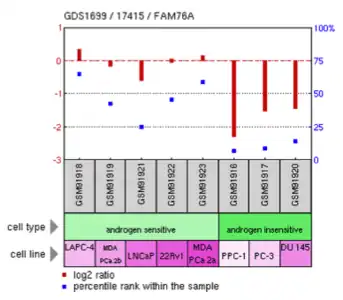

Experimental data

Select data from three experiments involving FAM76A are shown below. In one experiment, CLDN1 over-expression in lung adenocarcinoma cells decreased FAM76A expression.[19] In another experiment, androgen insensitive prostate cancer cells were shown to have reduced expression of FAM76A compared to androgen sensitive cells.[20] Another experiment demonstrated that metaphase II oocyte cells were shown to have more expression of FAM76A compared to control cells.[21]

- Selected NCBI Geo Data

Expression of FAM76A in Homo sapiens androgen sensitive and insensitive prostate cancer cell lines

Expression of FAM76A in Homo sapiens androgen sensitive and insensitive prostate cancer cell lines -